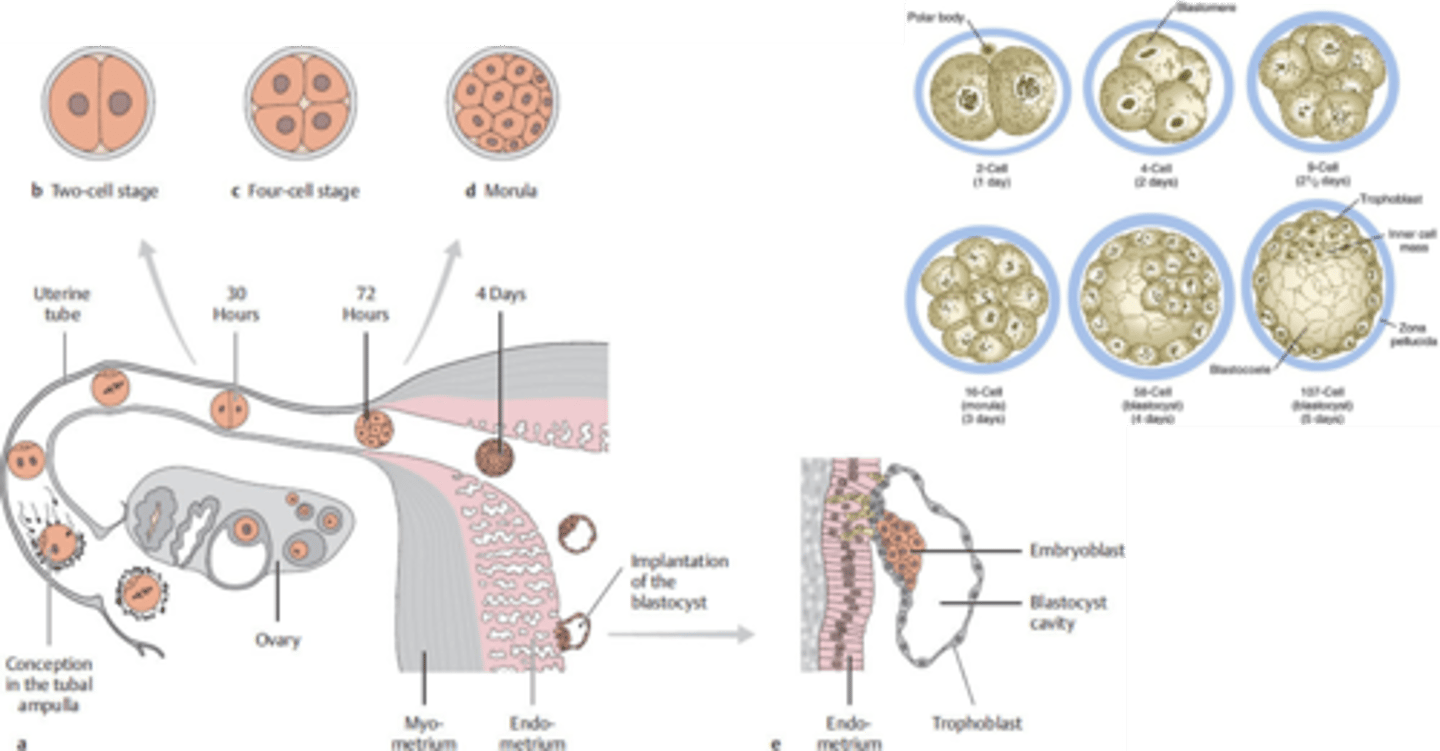

when a zygote undergoes a series of mitotic divisions, this leads to a 16-cell called the __________. as the cell enters the uterus, a cavity begins to appear and leads to the formation of the ___________.

morula, blastocyst

the (morula/blastocyst/gastrula) will form an inner cell mass called the ____________ and an outer cell mass called the ___________

blastocyst

embryoblast (embryo proper)

trophoblast (contributes to placenta)

the inner cell mass of the blastocyst will differentiate into the __________ and _____________ which forms a __________ disc

hypoblast, epiblast, bilaminar